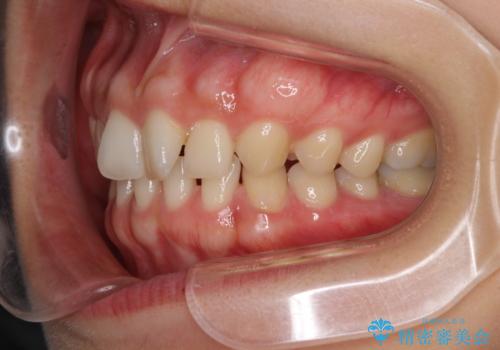

- 前歯の隙間と奥歯の目立つ銀歯を気にして来院された患者様です。

インビザラインにより下顎前歯の隙間を閉じるとともに、奥歯の咬み合わせを改善させることとしました。

矯正治療後には、銀歯のクラウンをセラミッククラウンへ替える補綴治療を行うこととしました。

左右奥歯の咬み合わせを変更させる必要があったため、治療期間は長くなることが予想されました。

1日22時間以上の装着時間をしっかりと守ってくださったので、順調に治療を進めることができました。